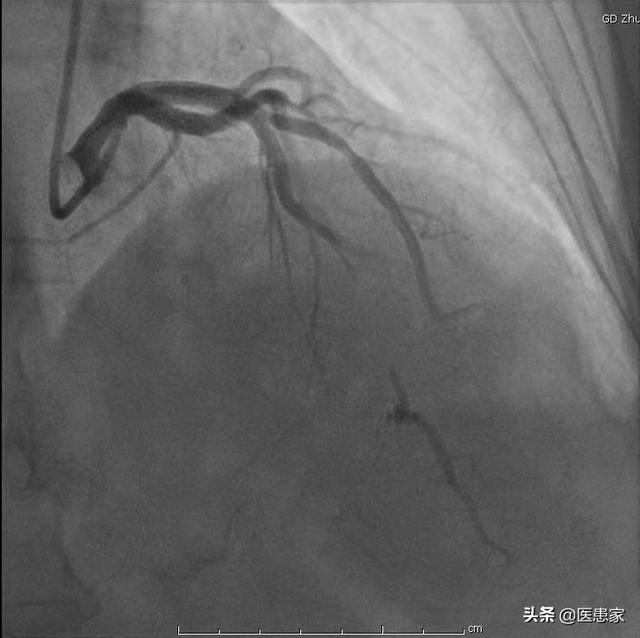

5. angiographie coronaire

- La coronarographie nécessite une hospitalisation et est invasive.

- Il a l'avantage d'être bien visible, ce qui est actuellement l'étalon-or du diagnostic coronarien, et si un certain examen révèle que l'obstruction est très grave, un stent peut être mis en place directement, sans qu'une seconde opération soit nécessaire.

- L'inconvénient est que les tests sont coûteux, nécessitent une hospitalisation et sont invasifs.

Mais ensuite.Depuis l'échographie, la tomodensitométrie coronaire et surtout la coronarographie, le diagnostic de la maladie coronarienne n'est plus un problème.Il s'agit notamment de pouvoir voir exactement quel vaisseau sanguin du cœur est bloqué et dans quelle mesure chez ce patient.

Il s'agit d'introduire un tube dans le cœur et d'effectuer une imagerie sélective qui permet de voir les vaisseaux sanguins à l'endroit voulu et de déterminer la quantité de vaisseaux sanguins obstrués.

Il est donc important de rappeler que la coronarographie est l'examen de référence pour le diagnostic de la maladie coronarienne, tandis que la tomodensitométrie coronarienne ne peut être qu'un test de dépistage.

6. angiographie coronaireLa coronarographie est un examen invasif qui reste l'"étalon-or" pour le diagnostic de la maladie coronarienne.. La localisation des lésions sténosées peut être identifiée et leur étendue estimée. Il est généralement admis qu'une réduction du diamètre de la lumière de 70 à 75 % ou plus affecte gravement l'apport sanguin.

3. Coronarographie : si l'angiographie coronarienne est l'étalon argent pour le diagnostic de la maladie coronarienne, nous appelons la coronarographie l'étalon or, qui ne doit avoir l'opinion de personne, c'est le test le plus précis pour confirmer le diagnostic de la maladie coronarienne, il n'y a personne.

Tout d'abord, le test le plus fiable est la coronarographie, qui permet de déterminer clairement quel vaisseau sanguin du cœur est obstrué, l'étendue de l'obstruction, etc.

1、Coronarographie

Il s'agit de l'examen de référence pour la détermination de la maladie coronarienne. Il est utilisé pour confirmer le diagnostic de la maladie coronarienne et pour en préciser l'étendue. L'avantage est que le médecin peut observer visuellement si l'artère coronaire est ouverte ou s'il y a une plaque ou une sténose. Le processus opératoire peut également être réalisé en fonction de la situation, et le traitement par endoprothèse peut être mis en place en temps opportun.